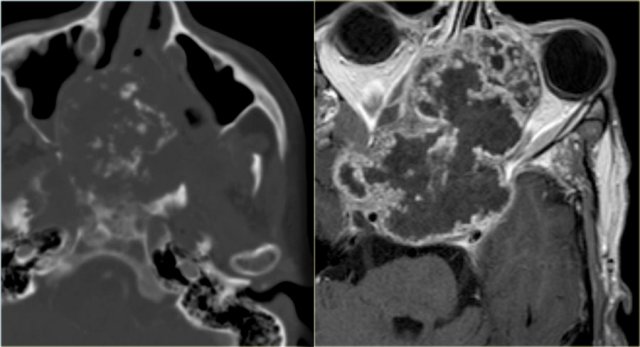

Chondrosarcoma (3)

On the left a massive chondrosarcoma of the skull base with extension to the nasal and paranasal cavities and orbita.

CT demonstrates irregular calcifications produced by the tumor.

A T1-weighted image after Gd shows typical septal and nodular enhancement.